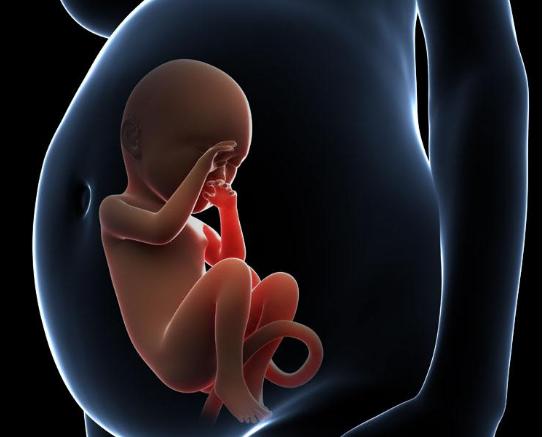

孕婦產檢做「四維」胎兒變「數學天才」

小夏這次去醫院做四維(超音波成像),通過屏幕顯示出來肚子裡的小傢伙正在擺弄著手勢,小夏仔細看了看,好像是數字「4」,她立刻拿出以前做四維的照片給醫生看。

原來小夏每一次做四維她都把胎兒在子宮裡的情況照下來,加上這次正好四次,而每次四維顯示出來的胎兒都在子宮裡擺出不同姿勢和手勢,但是連在一起就非常像小朋友「數數」,因為四次四維圖象連在一起胎兒的手勢正好是數字「1234」。